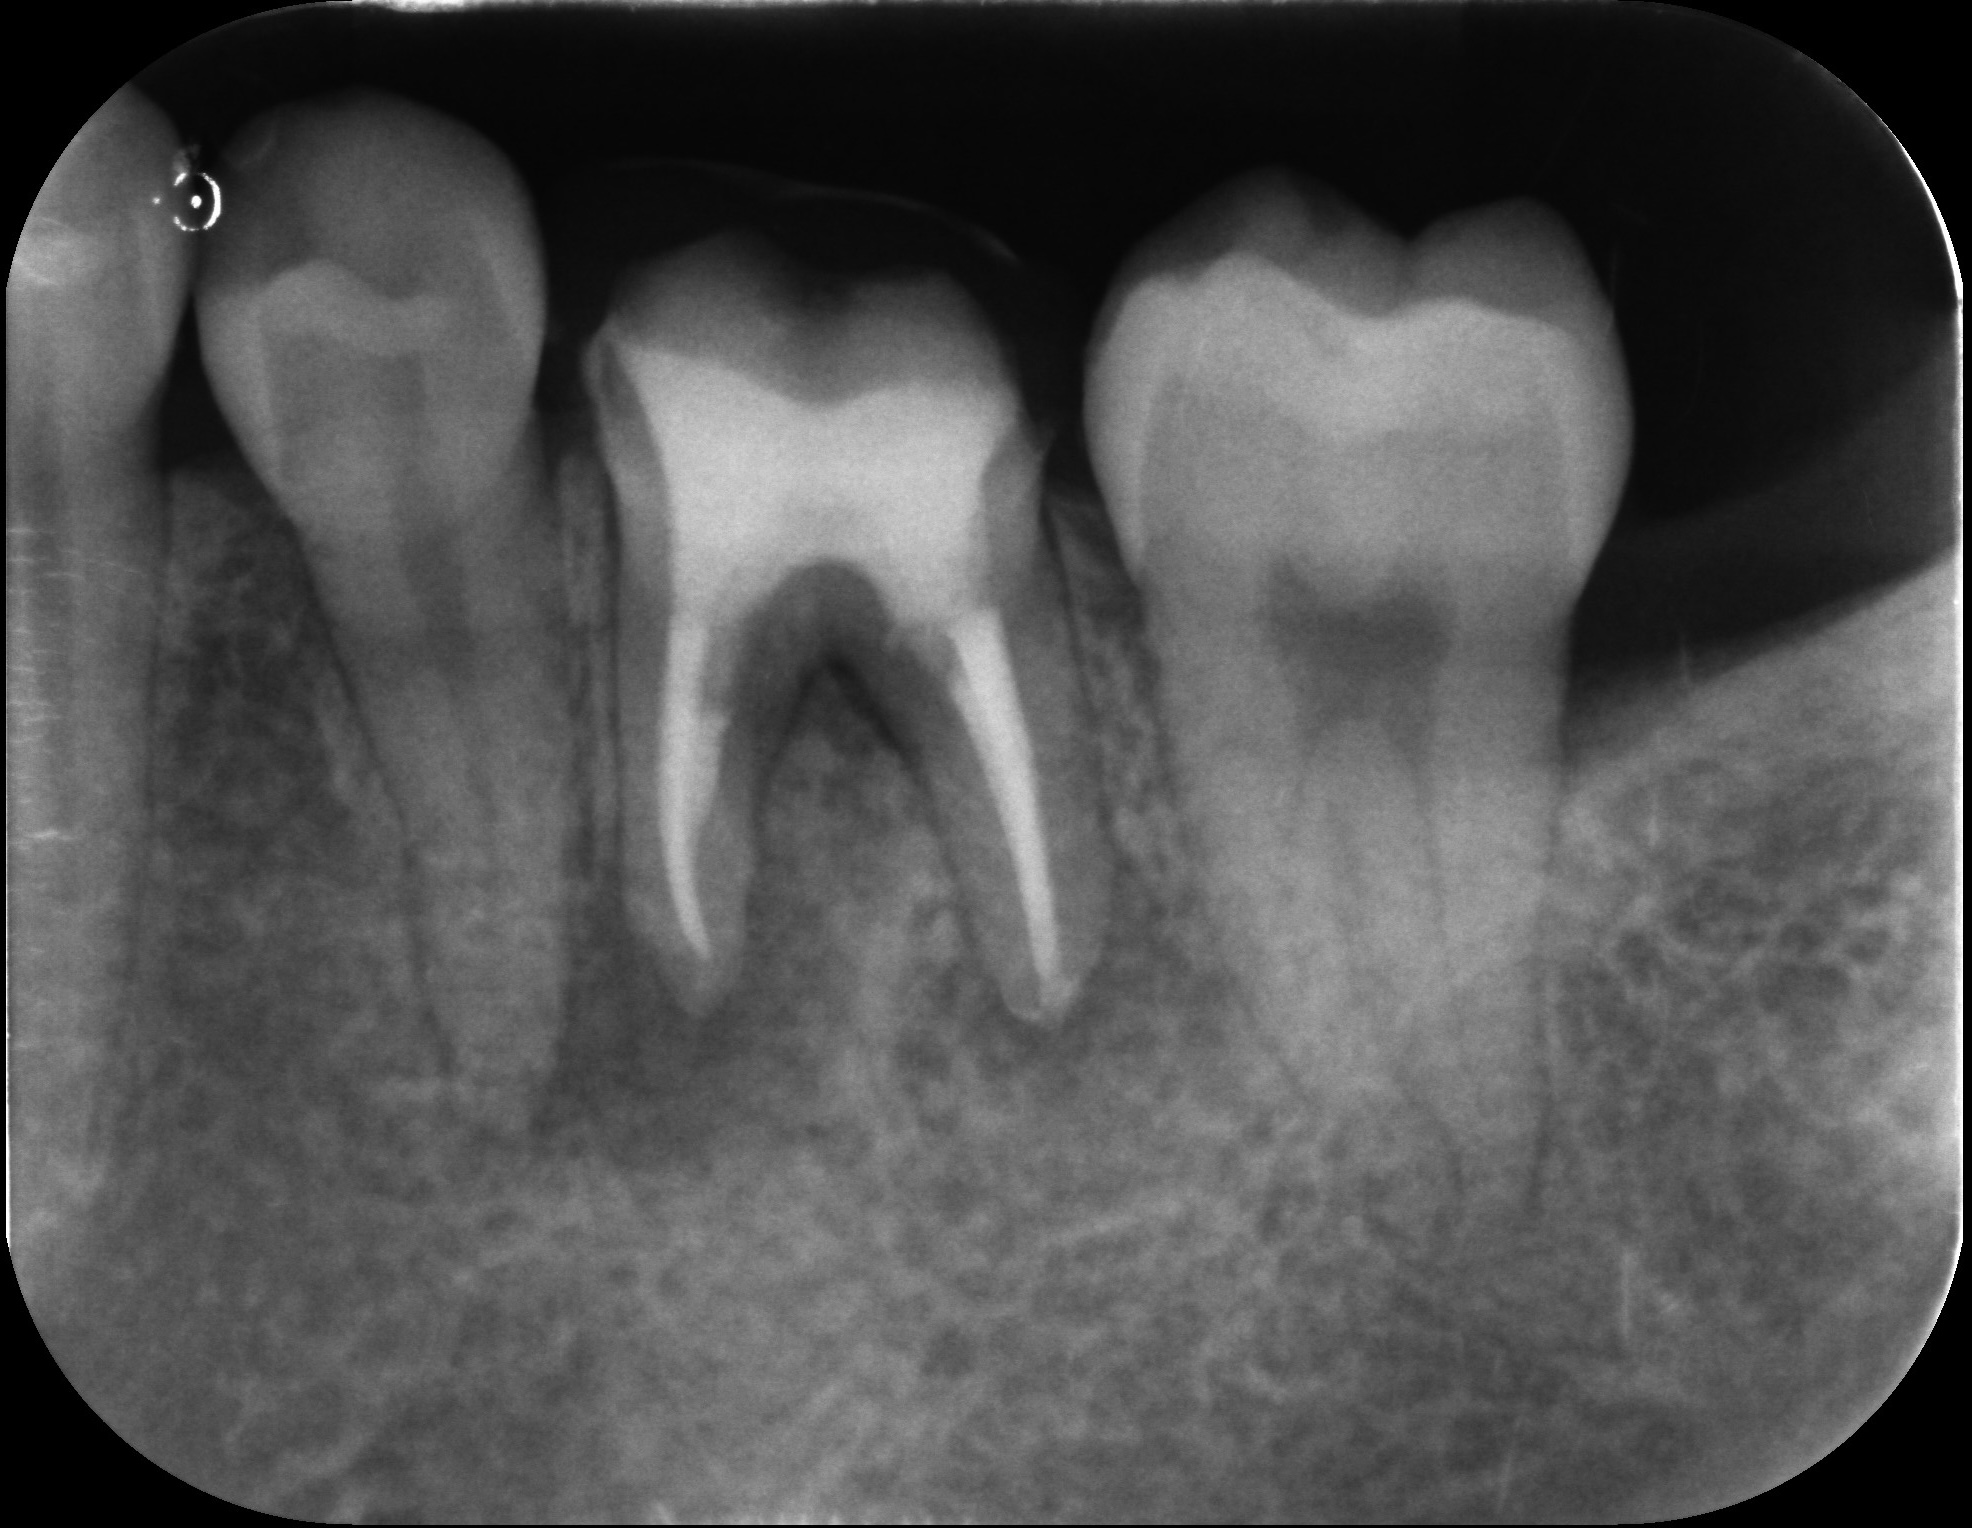

大臼歯の再根管治療を行った症例

タップで写真の拡大ができます。

Before&After(根管治療)

Before

Before&After(根管充填)

主訴

歯茎が腫れて、噛むと違和感がある

治療内容

再根管治療(大臼歯)

治療期間

1ヶ月

治療費用

165,000

治療の

リスク

処置中に歯肉縁下におよぶ重度のう蝕や破折を認めた場合、治療を中断する可能性があります。術後も症状が残る場合は追加の処置が必要になる可能性があります。